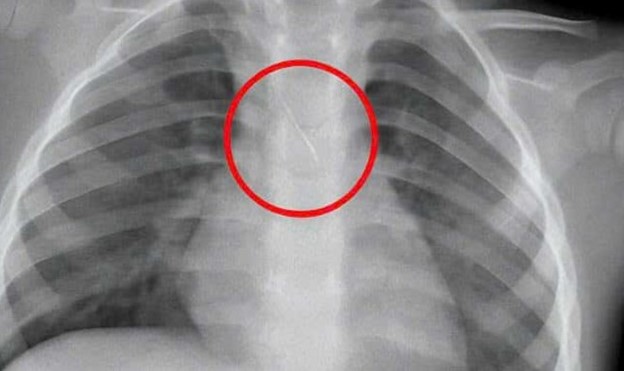

Kết quả chụp phim cho thấy, một dị vật kim loại dài khoảng 22mm nằm ở góc carina (vị trí chia đôi khí quản) đe dọa gây tắc nghẽn đường thở của trẻ. Ngay lập tức, các bác sỹ đã hội chẩn liên khoa và quyết định nội soi phế quản cấp cứu.

Dị vật được phát hiện có một đầu nhọn cắm vào 1/3 dưới khí quản, đầu còn lại nằm trong phế quản gốc trái, được xác định rất nguy hiểm.

Dị vật kim loại rơi vào đường thở. Ảnh: C.Châu